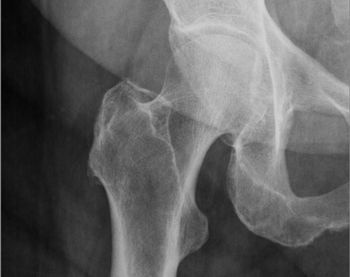

Despite lower length of stays, costs of hip fracture surgeries have been on the rise in recent years and a new study suggests it could be linked to increased hospital charges rather than increased surgeon charges.

A Mass General-led analysis of claims data indicates less than 1-in-10 patients who suffer a hip fracture were prescribed an osteoporosis treatment in the next 6 months, while also providing data on trends in prescribing practices of newer agents.